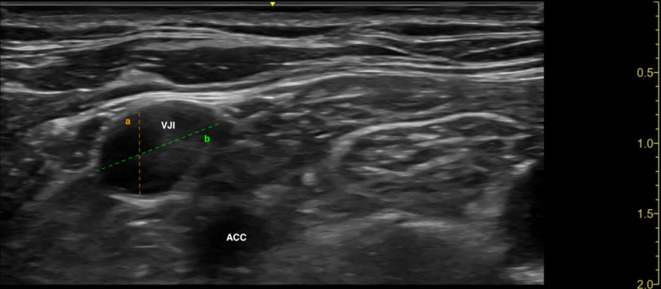

Results: A total of 200 subjects were equally divided between Group A and Group B. For the primary outcome, there was no significant difference in first attempt success rate (Group A: 79, Group B: 77, p = 0.434). Secondary outcomes, including complications and catheter functional time, did not differ significantly between the groups. However, the novel technique demonstrated a significantly faster procedure time (Group A: 315 s, Group B: 330 s, p = 0.016). Notably, the novel approach was linked with significantly larger IJV diameter measured during the procedure (Group A: 18.2 mm, Group B: 12.1 mm, p < 0.001).